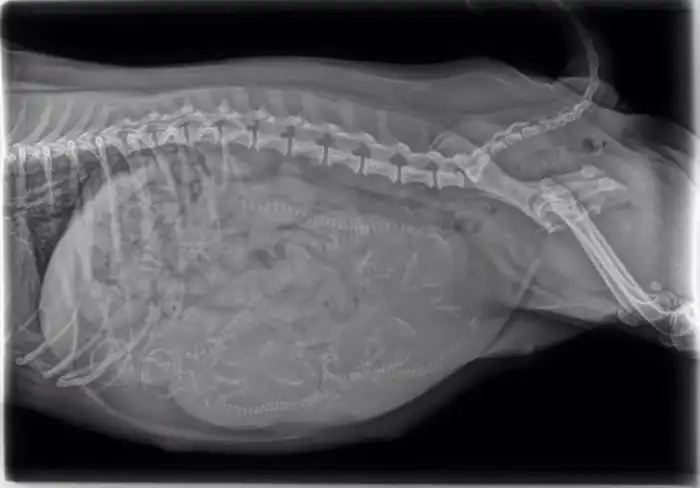

16. Беременная собака - внутри пять щенков